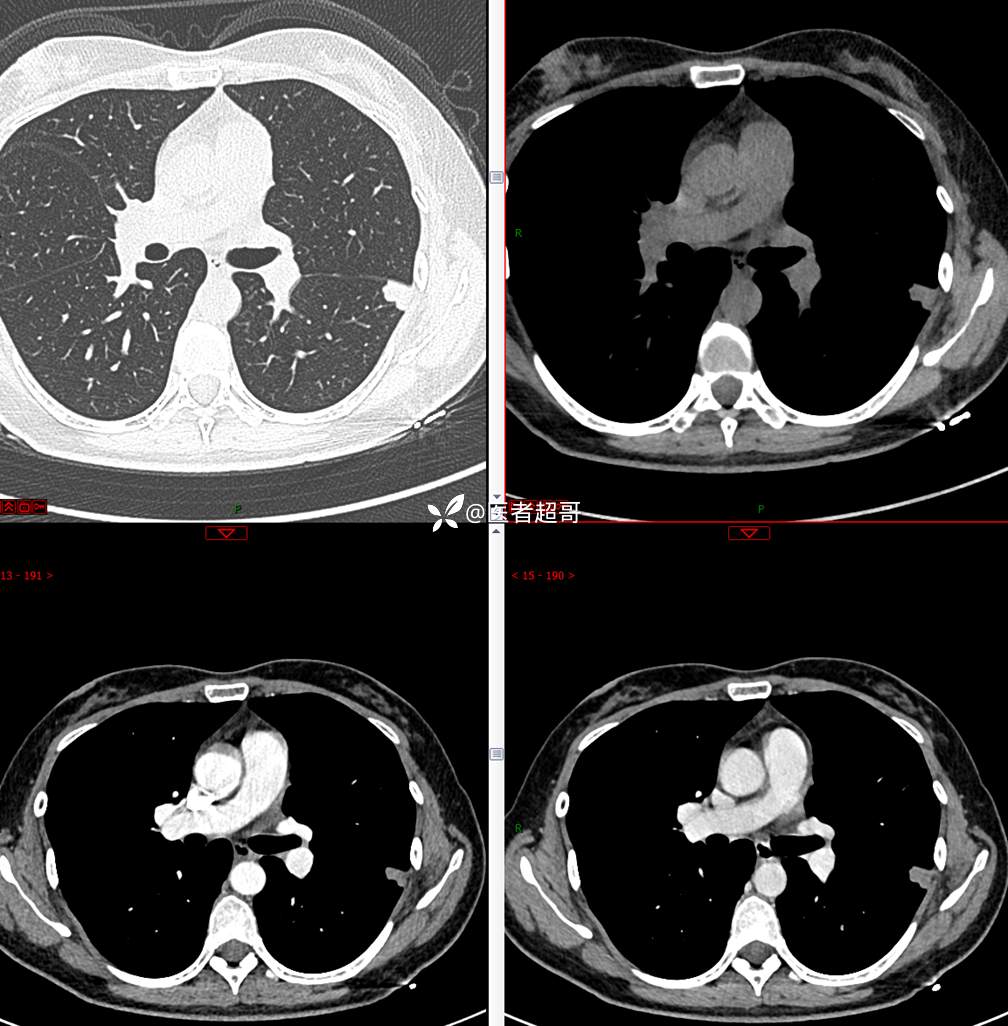

【影诊笔记705】查体发现肺肿物2月余,请诊断分析~~~

主 诉:查体发现肺肿物2月余

现病史:患者于2月余前行X线及胸部CT示:左肺结节。当时患者无明显不适,行抗炎治疗后复诊。于我院查胸部(肺)CT平扫示:左肺下叶实性小结节,请结合临床及原片,必要时进一步检查;双肺钙化灶右肺上叶微结节,建议随诊肝内钙化灶,门诊以“肺肿物”收入院。患者自发病以来,咳嗽咳痰,无痰中带血,无咯血,无胸闷胸痛,无心慌气短,无发热盗汗、无全身乏力,无头痛头晕,无恶心呕吐,无腹痛腹胀,无声音嘶哑及呛咳。患者自发病以来,神志清,精神可,饮食可,睡眠良好,大小便正常,近期体重未见明显增减。